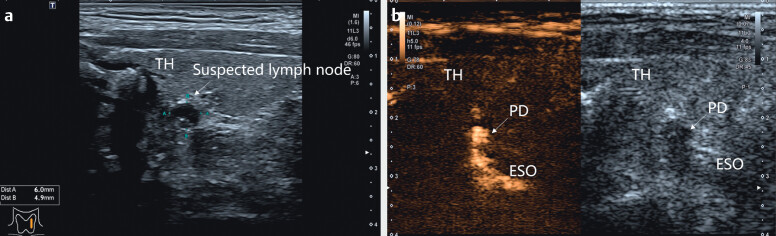

Abstract Image